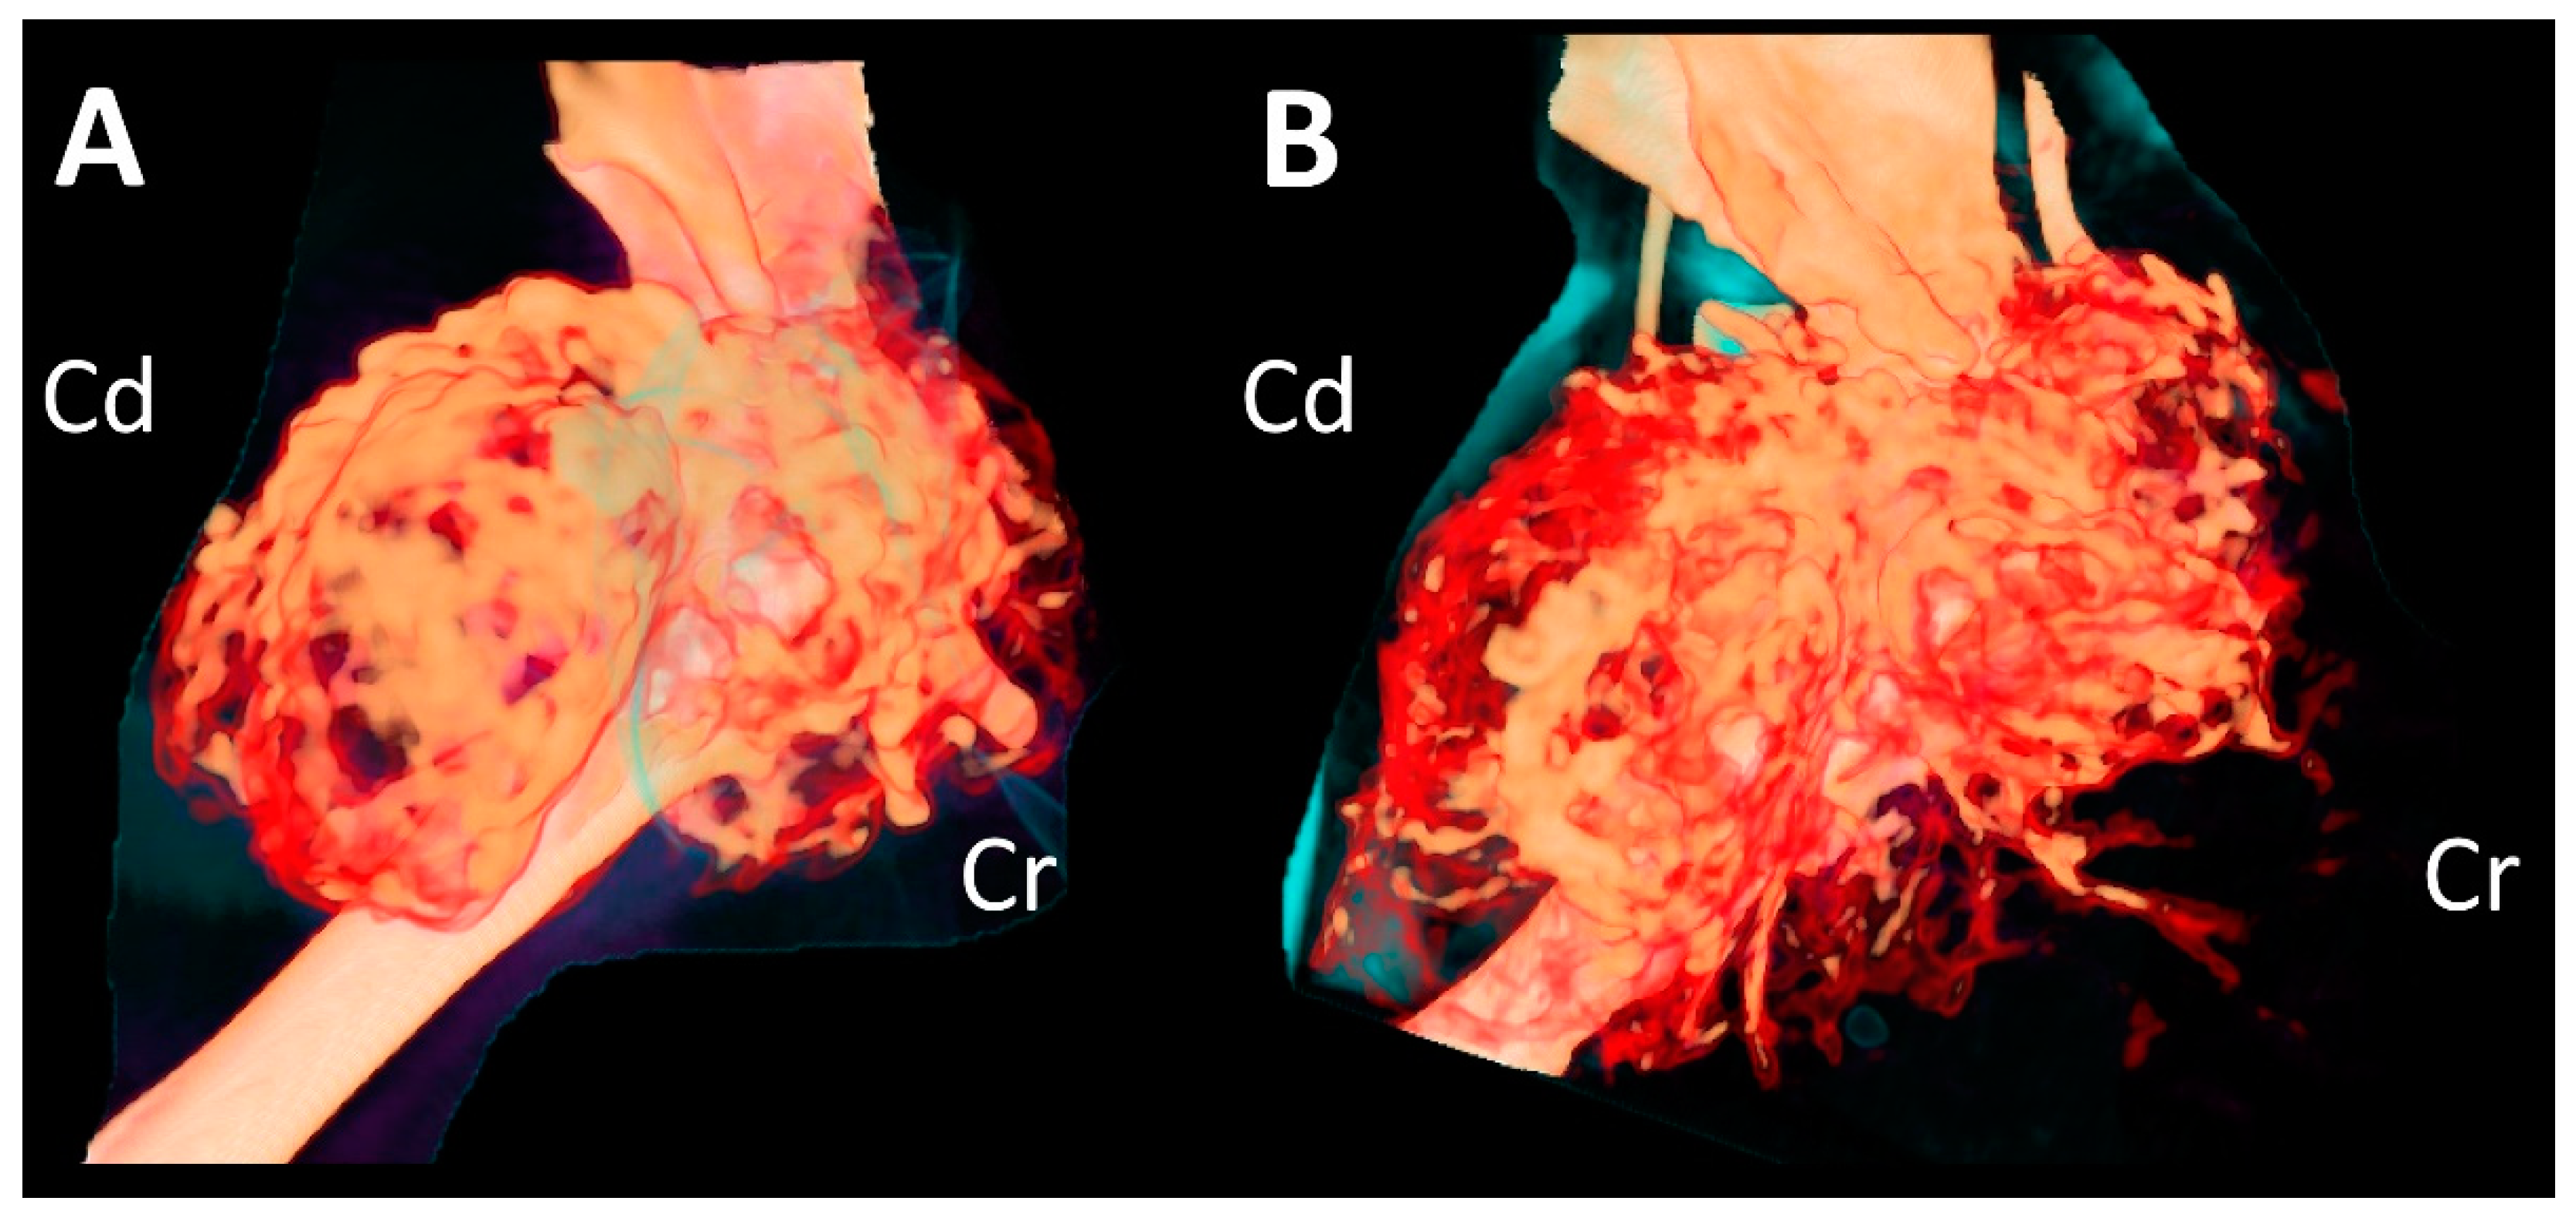

A complete blood count revealed severe anemia (hematocrit, 20.0%, reference range [RR] 30.3–52.3%). Four months after the initial presentation, a CT examination was performed again prior to the surgery (Figure 2C,D). Compared to the CT findings on initial examination, the mass had expanded dramatically in various planes. The overall thickness of the cortex of the mass had decreased, showing greater destruction of the medulla. Cortical destruction of the acromion and glenoid cavity was also identified, showing a more irregular surface due to the periosteal reaction. On three-dimensional volume-rendered images, osteolytic changes in the cranio-proximal region were more prominent, resulting in poor lesion margination at the time of the second presentation. In addition to the osteolytic changes, spiculated osteoid and areas of marked contrast enhancement were clearly visible, suggesting vascular proliferation in the surrounding soft tissue (Figure 3). The ipsilateral axillary lymph node had enlarged (1.9 cm × 1.75 cm × 0.79 cm) since the previous examination.

Figure 3. Three-dimensional volume-rendered images of the humeral mass at initial presentation (A) and second presentation (B), showing increased vascular proliferation around the mass.